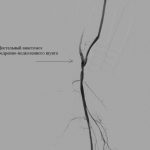

Операция прошла в несколько этапов в гибридной операционной Кардиососудистого центра, оснащенной новейшим медицинским оборудованием. Первым этапом выполнено бедренно-подколенное шунтирование реверсированной аутовеной стандартным способом. Затем проведена селективная ангиография через аутовену и дистальный анастомоз артерий голени, при этом выявлен критический стеноз (сужение) в начале передне-большеберцовой артерии (артерия голени). Следующим этапом проведением баллона через проводник к месту стеноза передне больше-берцовой артерии, устранено сужение сосуда баллонной ангиопластикой. На контрольном снимке кровоток восстановился ‒ значит, первая гибридная операция достигла своей цели.